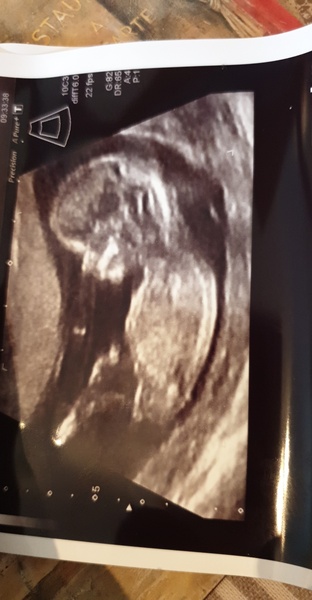

I’m 15+4 and EDD is Jan 9th. Second baby - I have a five year old daughter and it took us a few years to fall pregnant again after a miscarriage, so I’m thrilled and slightly stunned to be here again. We won’t find out the gender again this time, but I’m just feeling boy vibes, although I can’t imagine parenting a boy now! Even though that’s crazy as they’re all just tiny people.